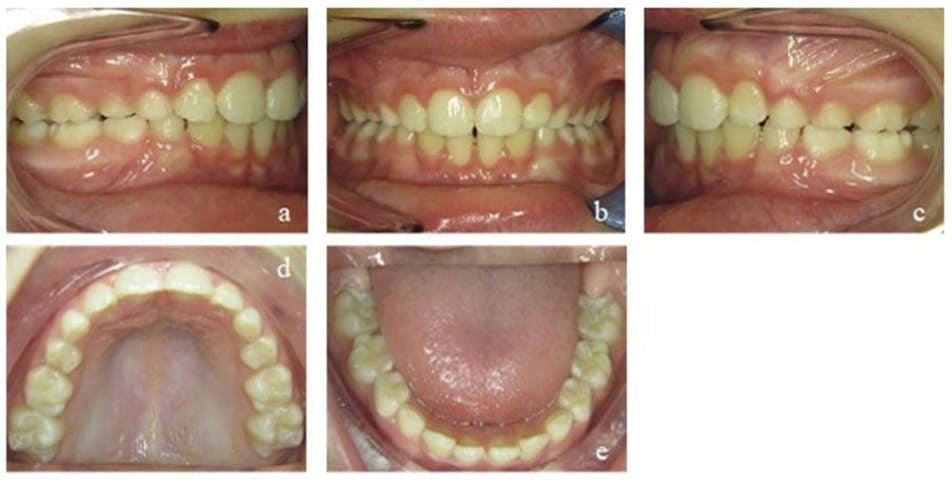

Figure 6: Case 1. Interims findings after 6 months of treatment. Frontal view of the occlusion (b), occlusion right (a) and left (c). Upper (d) and lower arch (e).

During the next treatment phase (another six months), the patient continued wearing the appliance and performing selected exercises as advised. The dental situation continued to improve, showing a physiological overjet of 2 mm with occlusal contact of all incisors and no crowding. However, the torque of the maxillary front teeth had still to be corrected (Figure 7). The strength of the tongue and its resting position on the palate also improved.

Figure 7: Case 1. Second interims findings after 12 months of treatment. Frontal view of the occlusion (b), occlusion right (a) and left (c). Upper (d) and lower arch (e).